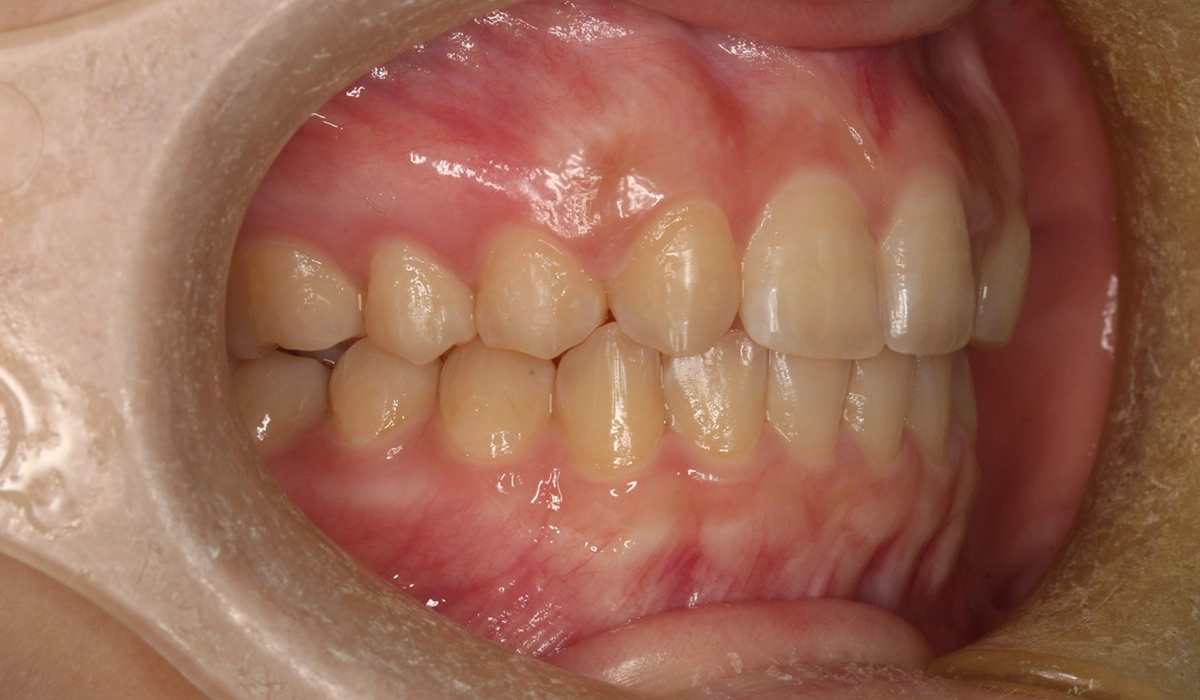

術後:右側

今回ご紹介する患者様は、上顎の歯並びのがたつきを気にされており、矯正検査後Ⅰ級叢生と診断いたしました。矮小歯があるため個性を生かして配列。

| 治療内容 | 上顎の歯並びのがたつきを気にされており、矯正検査後Ⅰ級叢生と診断。矮小歯があるため個性を生かして配列。 |